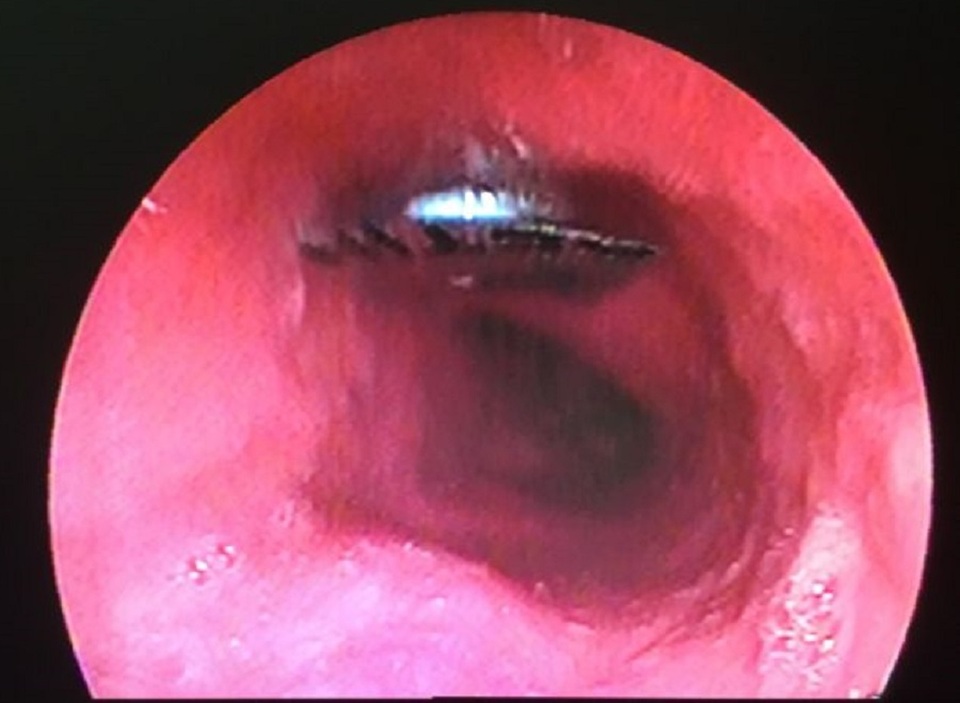

Viên thuốc còn nguyên vỉ nằm trong thực quản bệnh nhân được camera nội soi phát hiện

Khai thác bệnh sử của bác sĩ từ phía người bệnh ghi nhận, trước đó người bệnh có uống thuốc, khi nuốt xong thì bắt đầu thấy vướng ở cổ, cảm giác đau ngày càng tăng. Nghi ngờ bệnh nhân hóc dị vật, bác sĩ đã quyết định nội soi kiểm tra. Hình ảnh trên camera nội soi ghi nhận dị vật hình vuông dạng vỉ thuốc đang đóng vào thực quản, đoạn giữa.